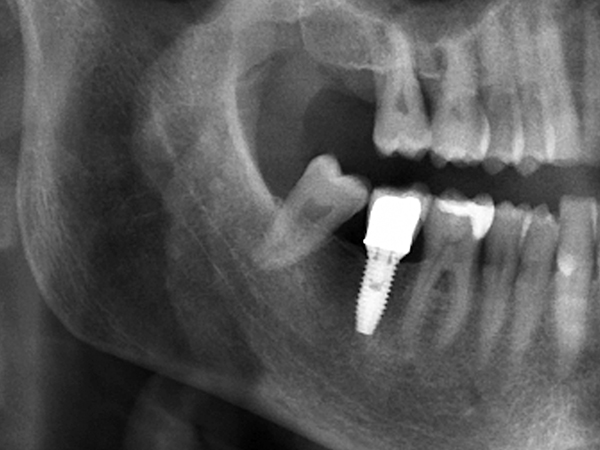

씹을 때 임플란트가 흔들리거나, 엑스레이 상에서 뼈가 많이 녹아 있는 것이 확인될 때에도 추가 치료 또는 재수술이 필요할 수 있습니다.

CT 촬영으로 뼈 상태와 염증 범위를 확인한 뒤, 감염 조직을 정리하고 필요 시 뼈 이식과 잇몸 치료, 보철물 교체를 함께 진행합니다.

정확한 재수술 시기와 방법은 CT와 구강 상태, 전신질환 여부를 종합적으로 평가한 후 결정하게 됩니다.